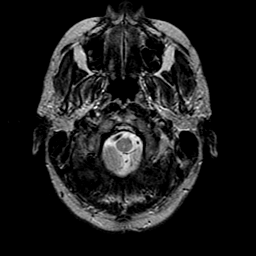

glioma overlay -- Slice #2

[Home][Help][Clinical] Slice 2